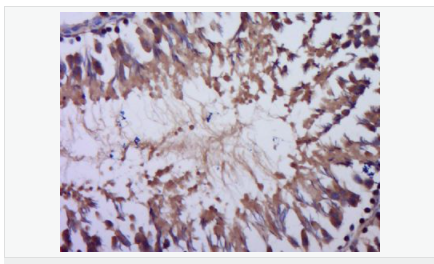

促黑細(xì)胞激素α抗體

Rabbit anti-alpha MSH Polyclonal antibody

英文名稱alpha MSH

中文名稱促黑細(xì)胞激素α抗體

別    名MSH Alpha; alpha melanocyte stimulating hormone; Alpha MSH; Melanotropin alpha; POMC; proopiomelanocortin;Alpha-MSH; Melanotropin alpha; proopiomelanocortin; COLI_HUMAN.

研究領(lǐng)域腫瘤  生長因子和激素

抗體來源Rabbit

克隆類型Polyclonal

交叉反應(yīng)Mouse,  (predicted: Human, Rat, Rabbit, )

產(chǎn)品應(yīng)用WB=1:500-2000 ELISA=1:5000-10000 IHC-P=1:100-500 (石蠟切片需做抗原修復(fù))

產(chǎn)品介紹This gene encodes a polypeptide hormone precursor that undergoes extensive, tissue-specific, post-translational processing via cleavage by subtilisin-like enzymes known as prohormone convertases. There are eight potential cleavage sites within the polypeptide precursor and, depending on tissue type and the available convertases, processing may yield as many as ten biologically active peptides involved in diverse cellular functions. The encoded protein is synthesized mainly in corticotroph cells of the anterior pituitary where four cleavage sites are used; adrenocorticotrophin, essential for normal steroidogenesis and the maintenance of normal adrenal weight, and lipotropin beta are the major end products. In other tissues, including the hypothalamus, placenta, and epithelium, all cleavage sites may be used, giving rise to peptides with roles in pain and energy homeostasis, melanocyte stimulation, and immune modulation. These include several distinct melanotropins, lipotropins, and endorphins that are contained within the adrenocorticotrophin and beta-lipotropin peptides. Mutations in this gene have been associated with early onset obesity, adrenal insufficiency, and red hair pigmentation. Alternatively spliced transcript variants encoding the same protein have been described. [provided by RefSeq, Jul 2008].